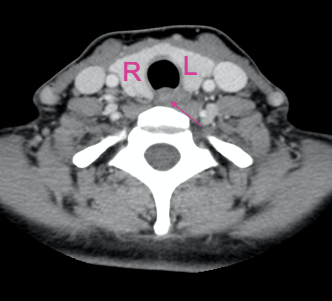

What is indicated by the arrow?

Oesophagus

Trachea

What is indicated by the arrows?

Common carotid arteries